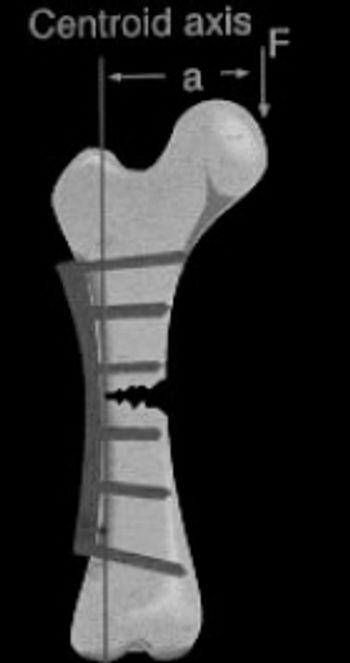

The patella is a type A (primary function is articulation) sesamoid bone located in the tendon of insertion of the quadraceps muscles. The origins of the quadriceps muscles are the proximal femur and immediately cranial to the acetabulurn (rectus femoris m.). The quadriceps m. follows a straight line, by necessity, to its insertion at the tibial crest.

Conservative treatment of CCL rupture is the same as treatment for DJD: exercise to build muscle, weight control and medications such as NSAID's and Adequan. Surgery is the most effective treatment for CCL tear if done before DJD is established. Conservative treatment is indicated if surgery is not chosen by the owner because of cost or other reasons.